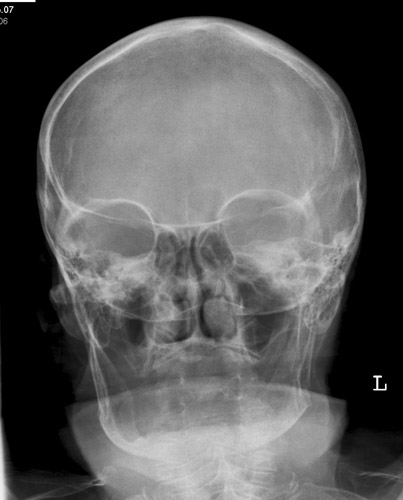

Orbita Übersicht

Fehler

Schräge Projektion, d.h. ungleicher Seitenabstand der Schädelkapsel zum Orbitarand. Die Orbitae stellen sich ungleichmäßig dar. Die Außenränder der Orbitae lassen sich nicht richtig vergleichen.

Abhilfe

Der Kopf war zwar richtig für eine Orbita gelagert, doch etwas nach links verkippt. Bei klinischer Relevanz müsste noch mal eine richtig orthograde Einstellung erfolgen.